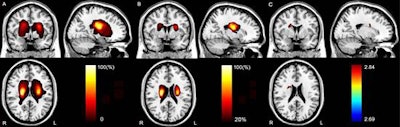

MR images provide a lesion incidence map (A) in patients with acute stroke. The map (B) also shows regions in which at least 10 patients had a lesion. Color bar denotes the probability of lesion distribution. The brain region (C) also is correlated with attention deficit in the voxel-based lesion-symptom mapping (VLSM) analysis. Color bar denotes the t-values. Images courtesy of Radiology.

VLSM results showed that the patients' delayed response time correlated with an acute stroke lesion in the right caudate nucleus and nearby white matter. DTT showed that the lesion was found in the right thalamic- and caudate-prefrontal pathways.